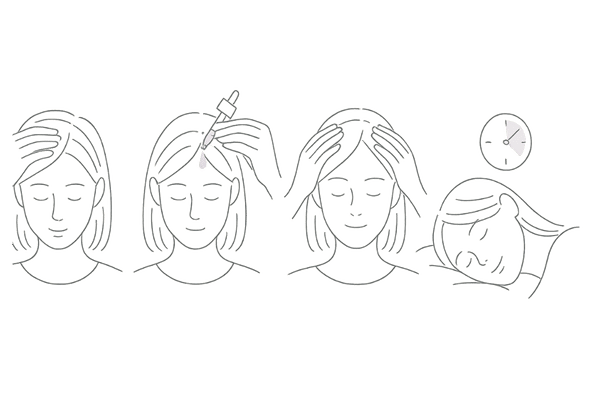

外用薬の塗布量と回数の基本

ミノキシジル外用薬は、原則として1日2回(朝と夜)、薄毛が気になる部分を中心に頭皮へ直接塗布します。

1回の使用量は、製品によって定められた規定量(多くは1ml)を守ることが大切です。量が多すぎると副作用のリスクが高まり、少なすぎると十分な効果が得られません。

容器の指示に従い、毎回正確な量を塗布する習慣をつけましょう。

塗布する際の注意点とコツ

ミノキシジルは髪の毛ではなく「頭皮」に塗る薬です。塗布する際は髪をかき分けて、薬液が直接頭皮に届くように意識してください。

指の腹を使って、塗布した部分を軽くマッサージするように馴染ませると、浸透を助ける効果が期待できます。ただし、爪を立てて頭皮を傷つけないように注意が必要です。

また、塗布後は薬液が乾くまで、少なくとも20〜30分は時間を置くのが望ましいです。

すぐに就寝すると薬液が枕などに付着し、効果が薄れるだけでなく、意図しない部分の多毛症を引き起こす可能性もあります。